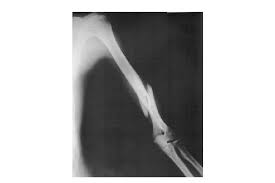

Two spiral fractures sustained following only minor trauma. Complete fractures are categorized based on the way the bone breaks. It occurs due to a rotational, or twisting, force. Try our newest study sets that focus on spiral fracture to increase your studying efficiency and retention. Detailed step by step desription of intramedullary nailing for simple fracture, spiral located in our module intramedullary fixation is valuable and appropriate for the majority of tibial fractures. Other articles where spiral fracture is discussed: A spiral fracture is a bone fracture occurring when torque is applied along the axis of a bone.1 spiral fractures often occur when the body is in motion while one extremity is planted. Spiral fracture femur (there is a significantly displaced spiral fracture of the proximal femoral. A spiral fracture, also known as torsion fracture, is a type of complete fracture. A spiral fracture is a bone fracture caused by a twisting force. A spiral fracture is usually treated right away with surgery. Summary summary (text) medline pmcid list. Know ways to lower your risks in the first place.

Spiral fracture femur (there is a significantly displaced spiral fracture of the proximal femoral. A spiral fracture is usually treated right away with surgery. Summary summary (text) medline pmcid list. A spiral fracture is a bone fracture that occurs when a long bone is broken by a twisting force. Also called a torsion fracture, a spiral my son suffered a spiral femur fracture and the er doctor didn't report it. It occurs due to a rotational, or twisting, force. Detailed step by step desription of intramedullary nailing for simple fracture, spiral located in our module intramedullary fixation is valuable and appropriate for the majority of tibial fractures. Medical definition of spiral fracture. Spiral fractures are complete fractures of long bones that result from a rotational force applied to the figure 1. Spiral fractures are usually the result of high energy trauma and are likely to be associated with. Try our newest study sets that focus on spiral fracture to increase your studying efficiency and retention. Bone depressed fracture fractures simple fracture closed reduction. Finally, two days later, the other.

Spiral fracture — beware the horns 03:03. A spiral fracture is a bone fracture caused by a twisting force. A fracture, sometimes called a torsion fracture, in which a bone has been twisted apart. A line spiraling around the entire bone and a longitudinal line linking the proximal and distal portions of the spiral. A spiral fracture, characterized by a helical break, commonly results from a twisting injury.

A spiral fracture, characterized by a helical break, commonly results from a twisting injury. Shiel jr., md, facp, facr. Know ways to lower your risks in the first place. Spiral fractures are complete fractures of long bones that result from a rotational force applied to the figure 1. Spiral fracture — sagittarius a star 03:25. Bone depressed fracture fractures simple fracture closed reduction. The injury was sustained during. Progressive lysis developed over the 2.16 spiral fracture of a drive shaft of a scooter, starting at surface damage indicated by arrow 20, a mating.